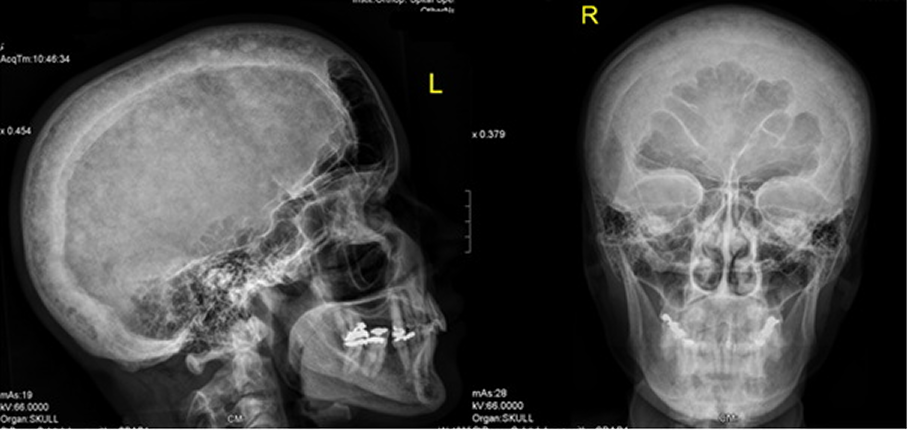

Sagittal T1-weighted MRI of the left knee showed no attachment of the posterior horn of the medial meniscus to the tibial plateau, but instead the meniscofemoral ligament (ligament of Wrisberg) joined the posterior horn of the meniscus to the lateral surface of the medial femoral condyle, i.e. discontinuity between the anterior and posterior horns, causing effectively the development of degenerative lesion of the posterior horn of the left medial meniscus (Figure 1 [Fig. 1]). On the bases of skeletal survey, weight bearing anteroposterior left lower limb radiograph showed varus deformity of the left lower extremity and narrowing of the medial knee joint and narrowing of the hip joint as well associated with unusual cortical thickening and bone enlargement. The angles of the frontal plane alignment were measured according to Paley: mechanical lateral distal femoral angle (mLDFA) = 106°, medial proximal tibial angle (mMPTA) = 85°, and the distal tibial angle (mLDTA) = 93°. These measurements were compared to weight bearing full length radiographs, which are considered to be the standard of reference for planning corrective surgery. The lateral distal left femoral angle measured 106°, which means approximately 20° deviation from the norms (Figure 2 [Fig. 2]). Skull radiographs showed the cotton wool appearance, disorganized trabecular with areas of sclerosis which are poorly defined and fluffy. Widening of the diploic space and relatively indistinct outer table, and the frontal sinuses are enlarged. No hyperostosis of the skull base was noted. These findings reflect the underlying pathologic changes of osteoblastic repair and are usually pathognomonic (Figure 3 [Fig. 3]). The patient underwent laboratory investigations with blood and urinary tests. Serum bone alkaline phosphatase was high (four times greater than the normal value), which is reflective of the rapid new bone turnover. Other laboratory studies showed normal levels of calcium, phosphate, PTH and vitamin D levels.